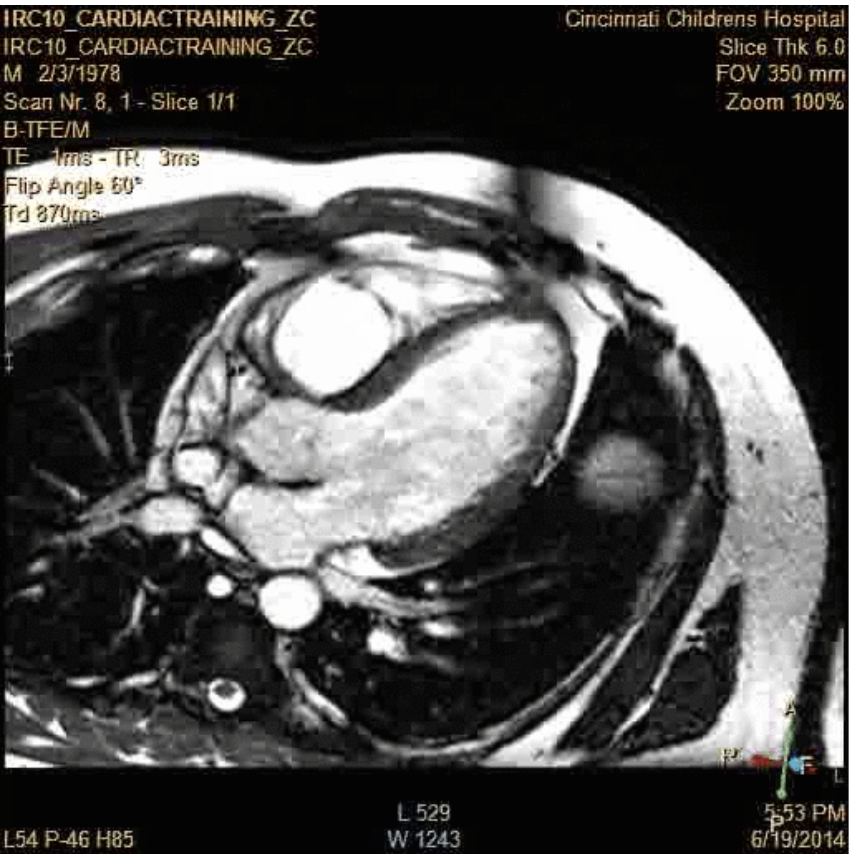

MRI of the Lungs​

• No ionizing radiation​

• Historically low signal from lung​

• Low density ​

• Fast signal decay (<1 ms)